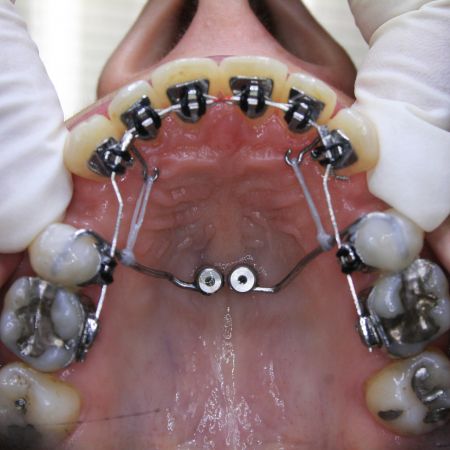

Während der Behandlung

Die ersten kleinen Backenzähne sind bereits entfernt und die festsitzende Zahnspange ist eingesetzt, in diesem Falle quasi unsichtbar auf der Innenseite der oberen Schneidezähne. Es ist wesentlich, daß die Lücken nur von vorne her geschlossen werden. Dies wurde sichergestellt, indem die Zähne hinter den Lücken über temporäre kleine Implantate am Gaumendach verankert wurden. In der Bildsequenz ist der Behandlungsfortschritt zu erkennen; der Lückenschluß war nach 1½ Jahren erreicht.